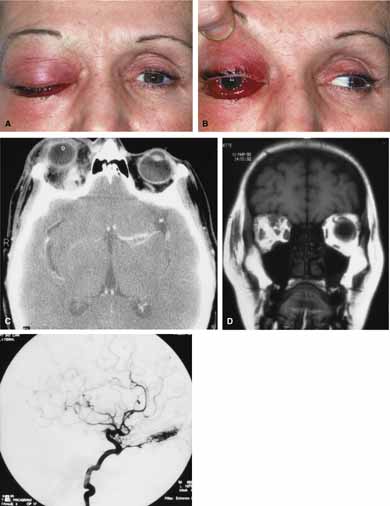

Cartoid cavernous sinus fistula (CCSF) is the most common arteriovenous malformation affecting the orbit and involves abnormal communication between a branch of the carotid artery and the cavernous sinus.79 The resulting high-flow fistula can produce proptosis (may be pulsatile), pain, engorgement of epibulbar veins (corkscrew configurations), limited extraocular motility, raised intraocular pressure and loss of vision (Fig. 12A and 12B). In many cases a bruit may be heard by the patient or examiner. The clinical features may mimic acute thyroid disease, but in contrast to thyroid eye disease, fistulas are usually unilateral. Seventy-five percent of fistulas occur as a result of head trauma; the rest occur spontaneously.79,80 Traumatic causes include head injury (penetrating or nonpenetrating) as well as iatrogenic causes including complications of carotid endarterectomy surgery. The spontaneous fistulas often occur in post-menopausal women. They may be the result of a congenital malformation (e.g., aneurysm or arteriovenous malformation) or associated with atherosclerotic changes, hypertension, collagen vascular disease, or childbirth. Some cases remain idiopathic. The spontaneous fistulas tend to be low-flow shunts in contrast to high-flow traumatic fistulas. Carotid cavernous fistulas can be subdivided as: (1) etiologic (spontaneous or traumatic); (2) hemodynamic (high or low flow), and 3) anatomic (direct or dural).79,80 CT and MRI are useful screening tests and may show dilation of the superior ophthalmic vein, increased extraocular muscle size and enlargement of the cavernous sinus (Fig. 12C and 12D). The definitive diagnostic test is bilateral selective internal and external carotid angiography.

Fig. 12 A. A 68-year-old female developed sudden proptosis (over 2–3 minutes), decreased vision, conjuntival injection, chemosis, and restricted motility. B. Multiple corkscrew vessels are seen secondary to engorgement of the epibulbar vessels. C. Axial computed tomography (CT) scan revealed proptosis and enlargement of the extraocular muscles. D. Axial computed tomography (CT) scan also revealed an enlarged superior ophthalmic vein.

Treatment may not always be required because 10% to 60% of spontaneous CCSFs will spontaneously close.79,80 The indication for intervention include visual deterioration, diplopia, intolerable bruit, headache, and proptosis causing untreatable corneal exposure.79,80 The goal is to cure the patient's symptoms without causing cranial nerve palsies or compromising carotid circulation. Methods of treatment involve various procedures to obliterate either the fistula, its afferent vessel, or its efferent vessel. High-flow fistulas are best treated with a detachable balloon because most will not close spontaneously. Closure may be facilitated by carotid compression applied by the patient. Fistulas between meningeal branches of the external carotid and cavernous sinus are supplied by single feeders and can be obliterated by selective embolization. Fistulas with shunts between the meningeal branches of both the internal and external carotid artery and the cavernous sinus require embolization of all feeding branches, which will eradicate fistulas in approximately 50% of cases. Alternatively, retrograde obliteration of the cavernous sinus may be required through a superior ophthalmic vein approach or internal jugular vein.59,81,82